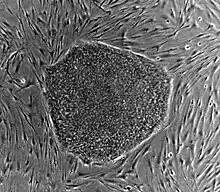

- les cellules souches pluripotentes, dont font partie les cellules ES (embryonnaires souches) : les cellules ES ne peuvent pas produire un organisme entier, mais peuvent se différencier en cellules issues de n'importe lequel des trois feuillets embryonnaires, y compris les cellules germinales. Elles ne peuvent à elles seules aboutir à la création d’un individu complet. Elles proviennent en effet de la masse cellulaire interne du blastocyste (au stade de 64 cellules) alors que le placenta qui nourrit l’embryon et le protège de tout rejet par le système immunitaire est produit par la couche cellulaire externe (ou trophectoderme). Elles ont vocation à former tous les tissus de l'organisme. Des cellules pluripotentes peuvent être artificiellement créées à partir de cellules différenciées grâce à l'ajout de quatre facteurs de transcription, on parle de cellules souche pluripotentes induites ;